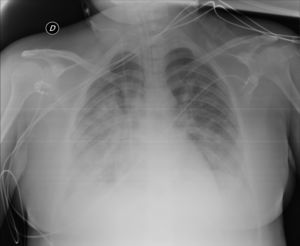

The patient was discharged to the ward on the fifth day, where inattention, apathy, and asymmetric mobilization of the right lower limb were noted. Although she showed steady respiratory and neurological improvement, a magnetic resonance imaging (MRI) study reported extensive hyperintense areas involving both the cortex and subcortical white matter. These areas were bilateral and symmetrical, but with greater extension in the right hemisphere and involvement of the parasagittal region and the bilateral parietal convexity, the bilateral frontal parasagittal region, and areas in the region of the right frontal superior convexity. Small areas of leptomeningeal uptake were identified, corresponding to slower, though unrestricted, intravascular blood flow. The finding was reported as posterior reversible encephalopathy (PRES) (Figs. 3 and 4). After the third day of hospitalisation, the patient presented episodes of HT, which were initially treated with labetalol and later with enalapril and amlodipine, and were diagnosed as peripartum hypertension. Nine days after re-admission to the ward the patient was discharged home after a total hospital stay of 18 days. Enalapril, amlodipine, and levetirazetam were prescribed as outpatient treatment.

Magnetic resonance imaging (T2-weighted and FLAIR images): Axial slices showing hyperintense areas with bilateral cortical and subcortical white matter involvement, more extensive in the right hemisphere. Involvement is seen in the parasagittal region and bilateral parietal convexity, and in the bilateral frontal parasagittal region. The image is suggestive of PRES.

None of the published cases of encephalitis have reported EEG results. Though nonspecific, the findings in our patient are compatible with viral encephalitis. Thromboembolism (common in COVID-19 patients) and cerebral haemorrhage/ischaemia had previously been ruled out with CT and angioCT without contrast. The MRI performed 2 days later (Figs. 3 and 4) with T1-weighted sequence in the sagittal plane and in T2 and FLAIR in the axial plane was compatible with PRES.